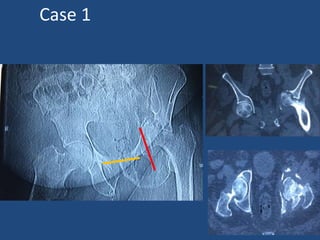

Preoperative Planning

• AP ; Lateral

• The shoot-through lateral

posterior column, which is often

obscured by the cup on other films.

• Judet oblique - pelvic discontinuity

• 3-d(CT) scans

– Pattern of the acetabular defect.

– Significant medial migration of the

acetabular component evaluate the

proximity of neurovascular structures.

Preoperative Planning • AP; Lateral • The shoot-through lateral posterior column, which is often obscured by the cup on other films. • Judet oblique - pelvic discontinuity • 3-d(CT) scans – Pattern of the acetabular defect. – Significant medial migration of the acetabular component evaluate the proximity of neurovascular structures.